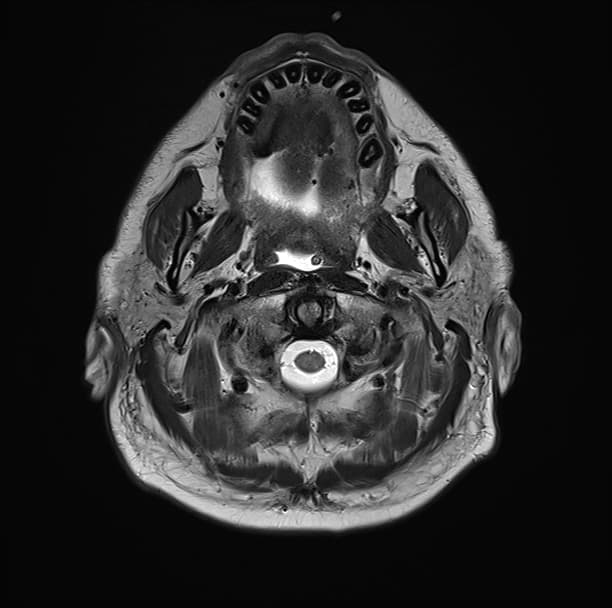

- Trên chụp CT sọ não có tiêm thuốc tương phản, thấy ngấm thuốc màng não mềm (leptomeningeal enhancement) và các nốt bắt thuốc (enhancing nodules) chủ yếu ở các bể nền (basal cisterns). Những hình ảnh này biểu hiện viêm màng não thể nền ưu thế (basal cistern predominant meningitis) kèm theo nhiều lao sợi (tuberculomas).

- Giãn cả hai não thất bên (both lateral ventricles) và não thất III (third ventricle), trong khi não thất IV (fourth ventricle) không giãn. Khi quan sát kỹ hơn, các tổn thương bắt thuốc (enhancing lesions) đang làm tắc lỗ ống nước (foramen aqueduct). Các hình ảnh này gợi ý giãn não thất do tắc nghẽn liên quan đến lao sợi (tuberculoma-related obstructive hydrocephalus).

- Các vùng giảm tỷ trọng (hypoattenuating areas) ranh giới không rõ ở cả hai nhân đuôi (caudate nuclei) gợi ý các vùng nhồi máu thể gai-đùi (lenticulostriate infarcts) do viêm mạch máu (vasculitis).

- Các đặc điểm hình ảnh điển hình (classic radiological features) của viêm màng não lao (tuberculous meningitis) bao gồm: dịch tiết nền bắt thuốc (enhancing basal exudates), giãn não thất (hydrocephalus) và các vùng nhồi máu ở các nhân nền (basal ganglia infarcts) do viêm mạch máu (vasculitis).